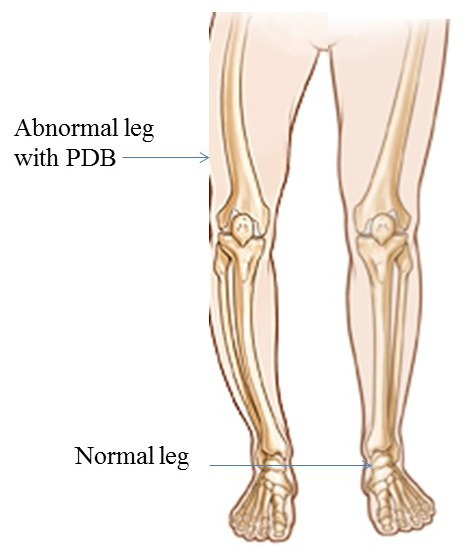

Figure 1

Representation of Paget’s disease of bone